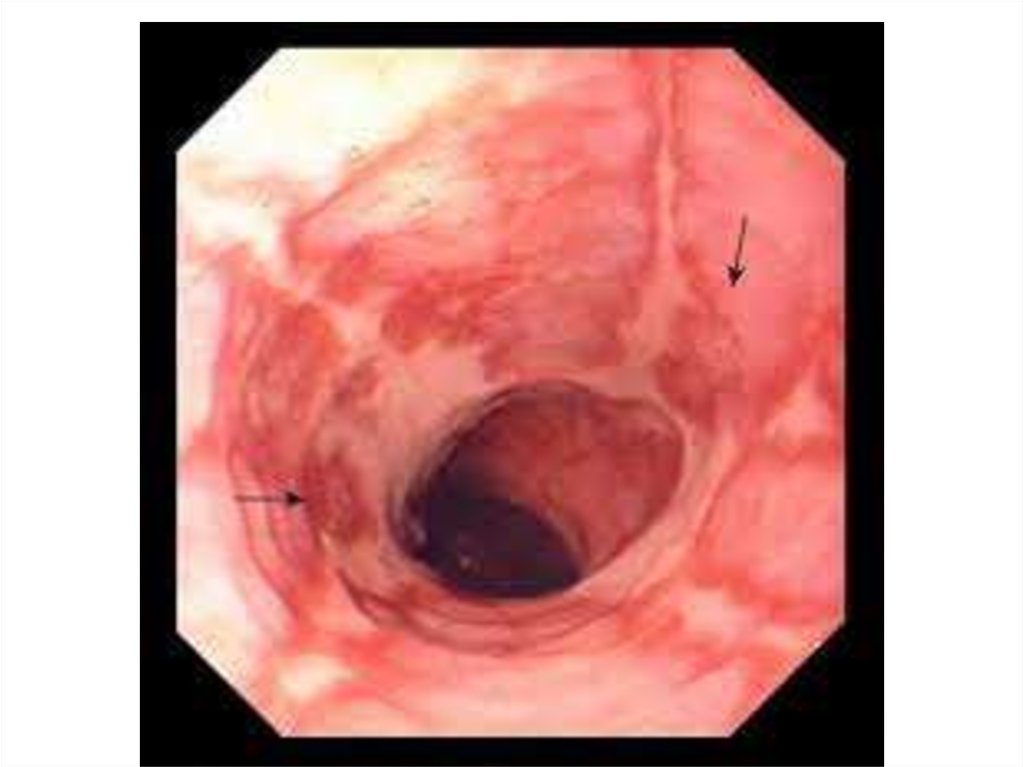

В зависимости от глубины

поражения различают 3 степени химического (и

термического) ожога пищевода.

• I степень характеризуется поражением

поверхностных слоев эпителия и выглядит как

гиперемия слизистой оболочки.

• II степень ожога приводит к некрозу

слизистой оболочки и образованию поверхностных язв.

• При III степени ожога поражается мышечный

слой с образованием глубоких язв,

отторжением слизистой оболочки и

кровотечением.